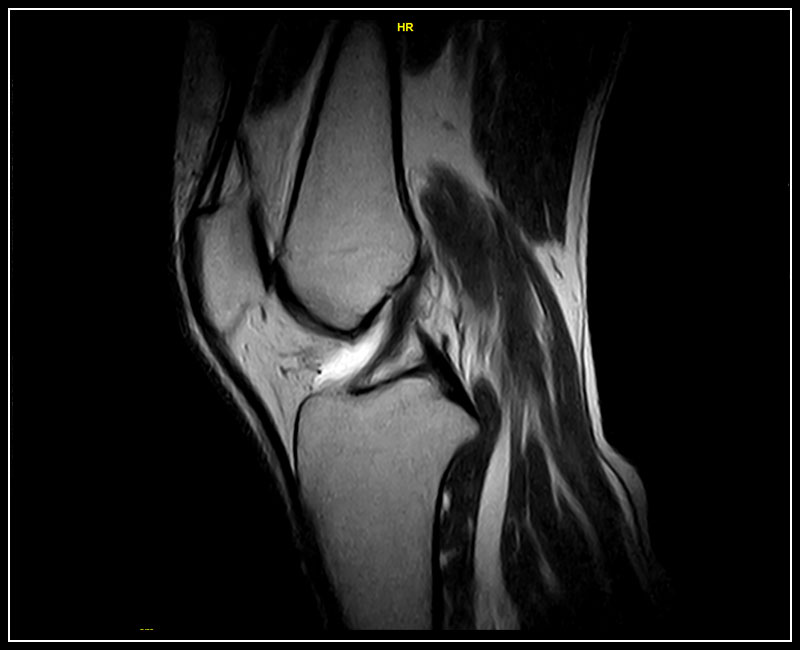

Klinické snímky